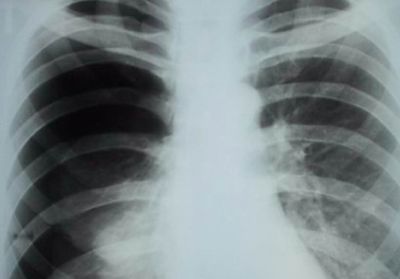

Пневмония

Пневмония — это воспаление легочной ткани, включая альвеолы, бронхи и соединительную ткань. Она может быть двусторонней, левосторонней или правосторонней. Воспаление правого легкого может вызывать боли в правом боку и спине.

При правостороннем воспалении легкого возникает тупая боль в правом боку, преимущественно в подреберье.

Филимошин Олег Александрович, врач-невролог городской поликлиники г. Оренбурга, отмечает, что при длительном течении заболевания боль может ощущаться в груди и спине со стороны пораженного легкого.

При появлении указанных симптомов необходимо обратиться к пульмонологу. Специалист проведет осмотр, соберет анамнез и назначит дополнительные диагностические процедуры, такие как:

- рентгенография;

- КТ;